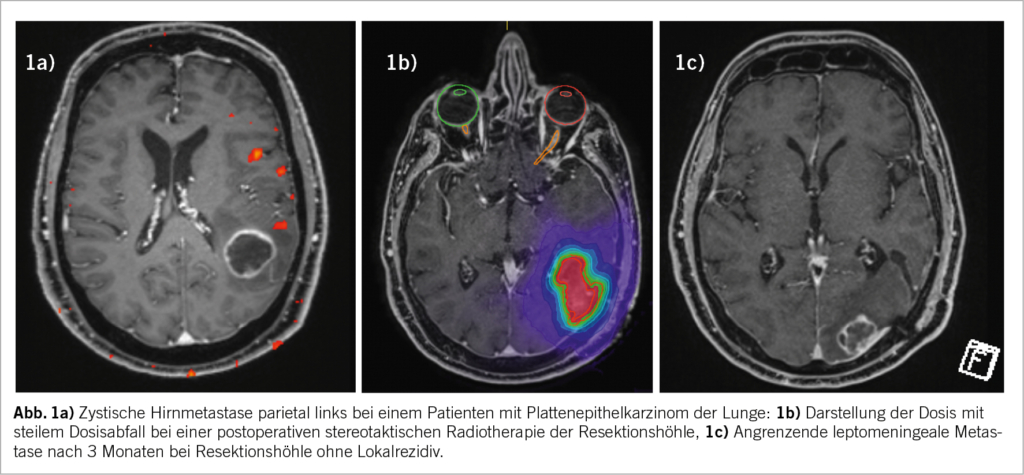

Die fraktionierte stereotaktische Strahlentherapie wird bei Hirnmetastasen von mehr als 2 cm bzw. 3 cm empfohlen. In einer Meta-Analyse wurde gezeigt, dass diese Strategie im Vergleich zur einfraktionierten Radiochirurgie mit einer signifikant niedrigeren Strahlennekroserate (23 % gegenüber 7 %) (7) und einer besseren lokalen Kontrollrate (91 % gegenüber 77 %) verbunden ist (8). Im Analogieschluss zur postoperativen Situation, in der die Resektionshöhle oft relativ gross ist, gilt deshalb in den meisten Zentren als Standardpraxis, eine Resektionshöhle nach einer metastatischen Resektion mit einer stereotaktischen Technik mit 3 bis 6 Fraktionen zu bestrahlen. Interessanterweise bietet diese Strategie in der postoperativen Situation möglicherweise eine höhere lokale Kontrollrate gegenüber der Radiochirurgie (87,3 % gegenüber 80 %) (9). Die Inzidenz von Radionekrosen in der postoperativen Situation beträgt in veröffentlichten Serien durchschnittlich 10,3 % (0-19 %) (10), wobei ein höheres Toxizitätsrisiko bei 3 Fraktionen beobachtet wurde (11). Es gibt auch eine Debatte über die angewandten «Sicherheits»-Säume (PTV Margin). Der Kompromiss zwischen besserer lokaler Kontrolle und häufigeren Strahlennekrosen dürfte bei 2 mm liegen (10).

Die noduläre leptomeningeale Metastasierung ist ein bekanntes Versagensmuster nach einer Hirnmetastasektomie mit einer Inzidenz von bis zu 18 % (9). Eine grössere Operationszugang und die Resektion mehrerer Metastasen, ein Zeitintervall zwischen Operation und fraktionierter stereotaktischer Bestrahlung von mehr als 50 Tagen, die Histologie Mammakarzinom und die infratentorielle Lage wurden als potenzielle Risikofaktoren für leptomeningeale Rezidive ermittelt (10). Eine diffuse leptomeningeale Erkrankung ist in der Regel eine Indikation für eine Ganzhirnbestrahlung, die mit den bekannten Toxizitäten wie neurokognitiven Beeinträchtigungen und Alopezie einhergeht. Das Bestreben, die leptomeningeale Rezidivrate zu reduzieren und gleichzeitig die lokalen Kontrollraten in der Kavität ohne zusätzliche Toxizität aufrechtzuerhalten, bildet die Grundlage für das Konzept die Radiochirurgie präoperativ anstelle von postoperativ durchzuführen. Es gibt zahlreiche Argumente für die präoperative Radiochirurgie von resektablen Hirnmetastasen. Wie bereits erwähnt, führt die Aussaat von Tumorzellen in die Zerebrospinalflüssigkeit während des neurochirurgischen Eingriffs zu einem häufigeren Vorkommen der nodulären leptomeningealen Metastasierung. Deshalb ist die Idee der Sterilisierung der Tumorzellen durch die präoperative Radiochirurgie besonders attraktiv. Die bereits publizierten retrospektiven Serien der präoperativen Radiochirurgie weisen eine Inzidenz der leptomeningealen Rezidive von nur 0-7 % (12,13) auf. Darüber hinaus stellt in der klinischen Praxis eine Konturierung der Operationshöhle nicht selten eine gewisse Herausforderung dar. Insbesondere sind die meningealen Resektionsränder nicht immer eindeutig zu definieren. Folglich resultieren diese und andere Faktoren in der Notwendigkeit der Anwendung von grösseren Margins und konsekutiv in einem grösseren Bestrahlungsvolumen des normalen Hirngewebes (insbesondere bei kleineren Hirnmetastasen) (14), (15). Im Gegensatz dazu ist die Volumendefinition bei der präoperativen Radiochirurgie wesentlich einfacher und der Sicherheitssaum kann auf 1 mm begrenzt werden. Des Weiteren ist die chirurgische Entfernung des bestrahlten Hirngewebes ebenfalls von Vorteil und senkt das Risiko für Radionekrose. Ein weiterer Vorteil bezieht sich auf die Möglichkeit der früheren Durchführung der Radiochirurgie von zusätzlichen und nicht operativ entfernten Hirnmetastasen sowie der Einleitung einer postoperativen systemischen Therapie. Wie die Machbarkeitsstudie PREOP–1 erwiesen hat (Manuskript in Vorbereitung) ist die neoadjuvante radiochirurgische Behandlung bezüglich zeitlichen Ablaufs und ohne relevant erhöhten Ressourcenaufwand gut möglich. Gleichzeitig hat die Machbarkeitsstudie keine relevanten Sicherheitsbedenken aufgeworfen. Die Gefahr einer falsch positiven Diagnose der Hirnmetastase durch die präoperative MRT ist zwar nicht vollkommen vernachlässigbar, aber dank der modernen multiparametrischen Bildgebung ist die Inzidenz deutlich reduziert. Der Nutzen der präoperativen Radiochirurgie wird aktuell im Rahmen der internationalen randomisierten Phase III Studie (PREOP-2), die eine Fraktion präoperativ mit fünf Fraktionen postoperativ mit dem primären Endpunkt «Inzidenz leptomeningealer Rezidive» vergleicht, weiter untersucht.